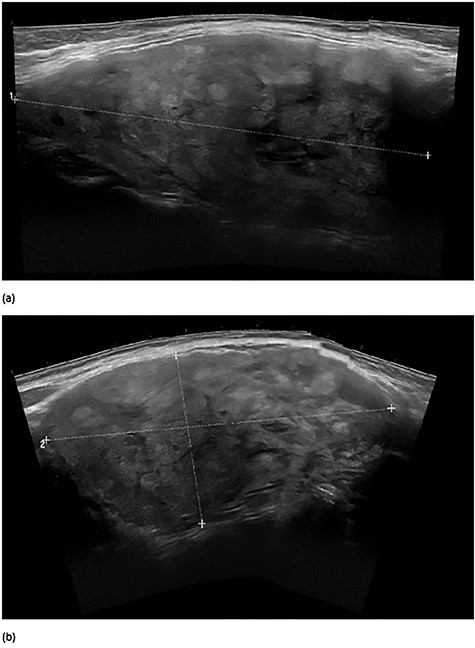

At initial presentation, she was undergoing chemotherapy but recently discontinued one of the agents due to thrombocytopenia. Initial work-up included thyroid-stimulating hormone and free T4 which were within normal limits. A surgeon performed thyroid ultrasound revealed a large 8.9 × 5.0 × 9.7 cm solid, isoechoic, homogeneous nodule without calcifications encompassing the right thyroid lobe and extending into the substernal/subclavicular location (Fig. 2). Fine needle aspiration of the large nodule revealed colloid and follicular groups consistent with colloid nodule or goiter. Given the large size and associated decreased diagnostic accuracy as well as tracheal deviation, excision was recommended after completion of her course of chemotherapy.

Preoperative surgeon performed right thyroid ultrasound images in longitudinal axis (a) and in transverse view (b). The large nodule measured 8.9 × 5.0 × 9.7 cm.